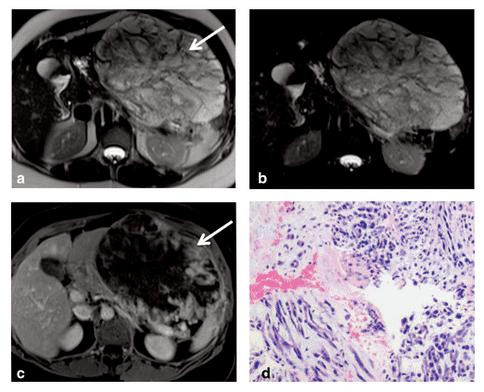

肠系膜肿瘤,图源:Wiley online library

Mesenteric masses: Approach to differential diagnosis at MRI with histopathologic correlation

https://onlinelibrary.wiley.com/doi/full/10.1002/jmri.24690